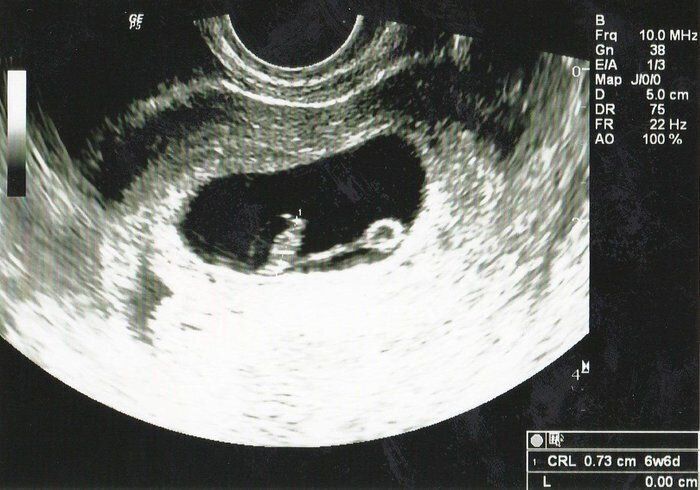

Tomomiさんの妊娠6週目のエコー写真 心拍確認できました

「ちゃんと大きくなっているかな?胎嚢の中に赤ちゃんは見えるかな?」不安な気持ちで内診台へ上がり、思わず手を組んで祈ってしまいました。先生のとっても嬉しそうな「おー、いたいた」という声にほっと胸を撫で下ろし、ピコピコ動くベビちゃん(胎児ネーム)の心拍を見ながら、「現実なのかな?」と信じられない気持ちでいっぱいでした。

私にとって4度目の妊娠陽性反応、そして初めての心拍確認!1つの大きな壁を乗り越えたと同時に、妊娠が継続するのかと、不安な気持ちと闘う日々も続くのでした…。